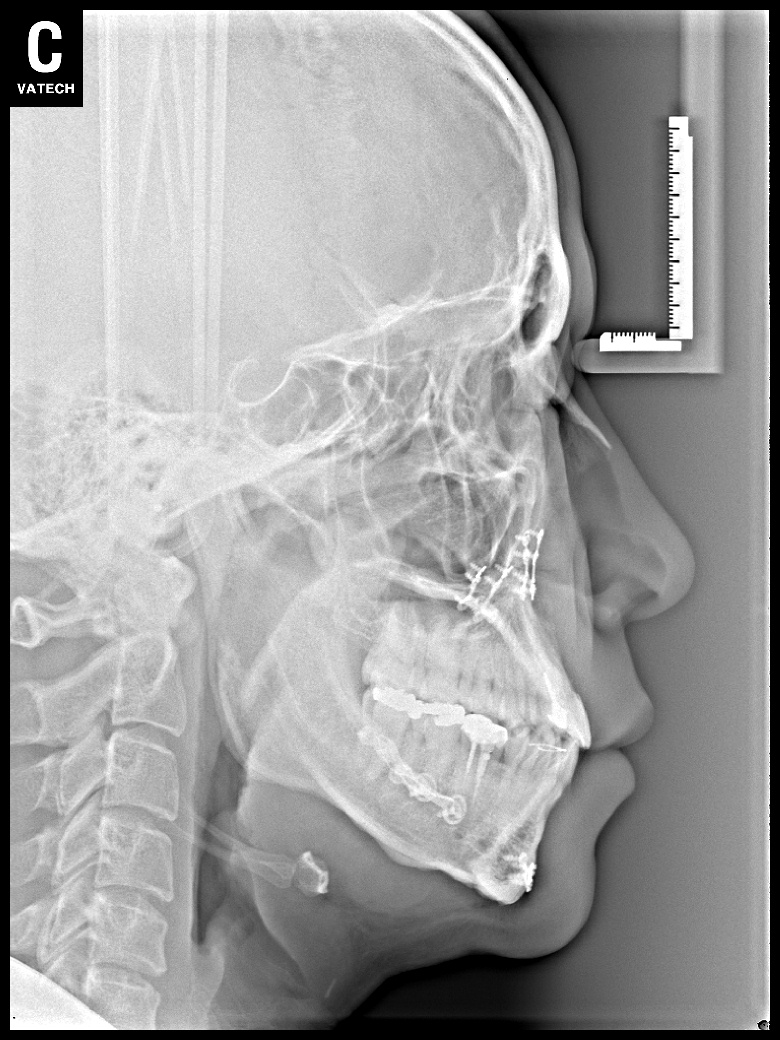

치료 전 사진입니다.